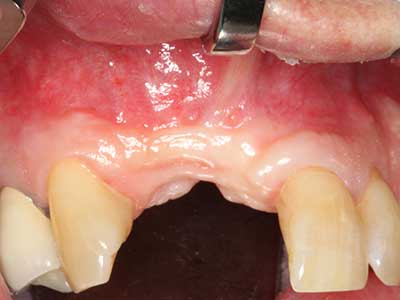

Piezo surgery has additional advantages when harvesting bone blocks. In addition to the high precision with osteotomy described above, the use of the thin saw tips specifically minimizes loss of material. Greater loss of material during harvesting can be expected with the thicker instrument tips, particularly when using Lindemann drills (Lakshmiganthan, Gokulanathan et al. 2012). The basal separation, which is necessary particularly for retromolar block transplants, is simplified by specially designed rectangular saws, with the result that piezo surgery is viewed as a precise, simple and safe procedure for harvesting retromolar bone blocks (Happe 2007) (Fig. 1-12).